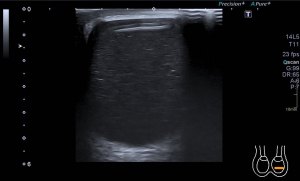

En esta última imagen te muestro la angiogénesis o neovascularización. Existe un aumento de aporte sanguíneo para reparar aquel tejido que está dañado. Esta angiogénesis o aumento de vascularización y por tanto Doppler podría ser secundario a un proceso de reparación mal gestionado por el tejido. Esta angiogénesis también podría estar en relación con aumentos del dolor en la zona y no significa que la patología cure antes. Gracias Javier. Gracias Amigo.